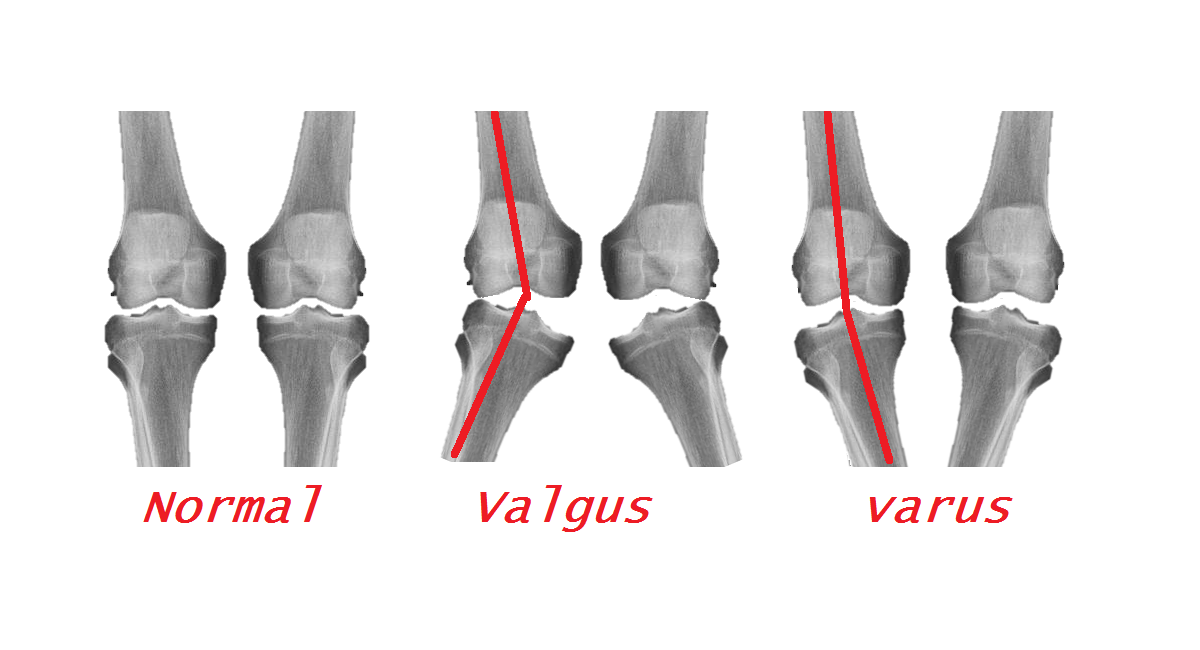

Dr. Kevin Darr is a respected Lecturer on Orthopedics and Regenerative Therapies. During the pandemic, Dr. Darr was able to have his research published in Regenerative Medicine an internationally viewed journal. On June 12, 2020 Dr. Darr presented his findings on “Effective Clinical Modulation of Knee Osteoarthritis Symptoms through Combined Cellular Therapy (Lipoaspirate, BMC and PRP)” at The OrthoBiologic Institute (TOBI) annual meeting.